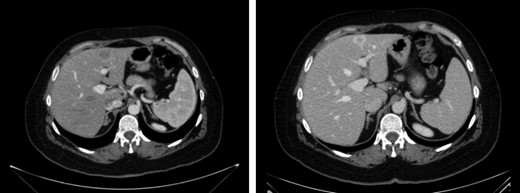

Ten months later, CT revealed two hepatic lesions (segment III of 3 cm and segment VII of 1 cm) (Fig. 2) The biopsy confirmed the original histology of SNUC. Chemotherapy with docetaxel 75 mg/m2, cisplatin 75 mg/m2 and 5 FU 750 mg/m2 every 3 weeks for 3 months was administrated. Because of minimal response was achieved after chemotherapy (Fig. 2) a non-anatomical metastasectomy was performed.

CT scan first relapse. Liver metastases: sIII and sVII 2.2 CT scan after neoadjuvant chemotherapy.